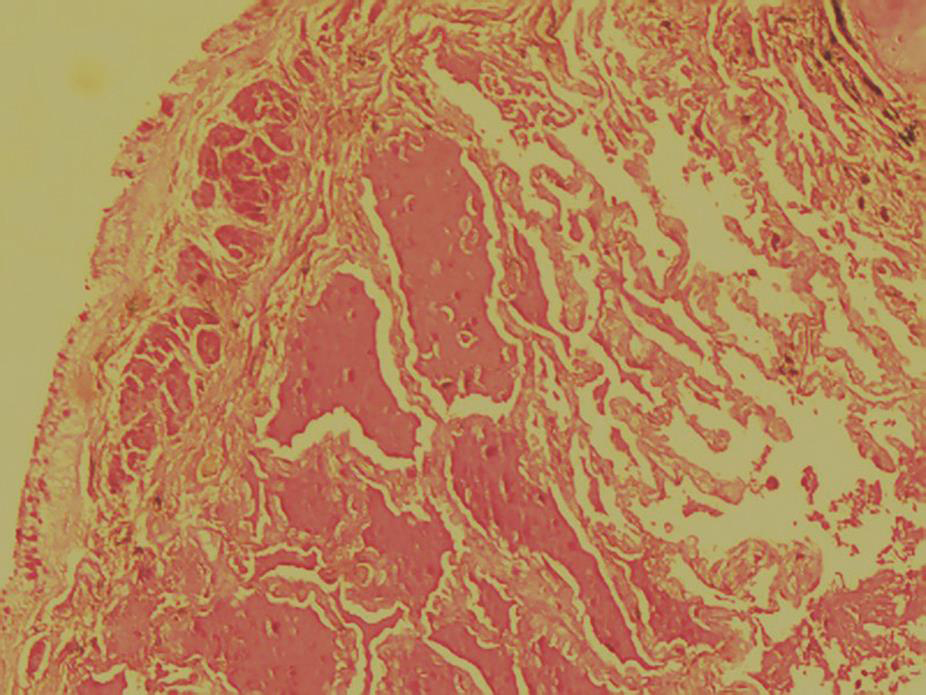

经支气管肺活检:肺支气管黏膜炎症不明显,肺泡腔扩张,腔内有红色渗出液(PAS染色阳性)(图11),肺泡间隔纤维组织轻度增生,间质少量慢性炎症细胞浸润,符合肺蛋白沉着症表现。

图11右下叶基底段肺组织病理表现(PAS染色,100×)